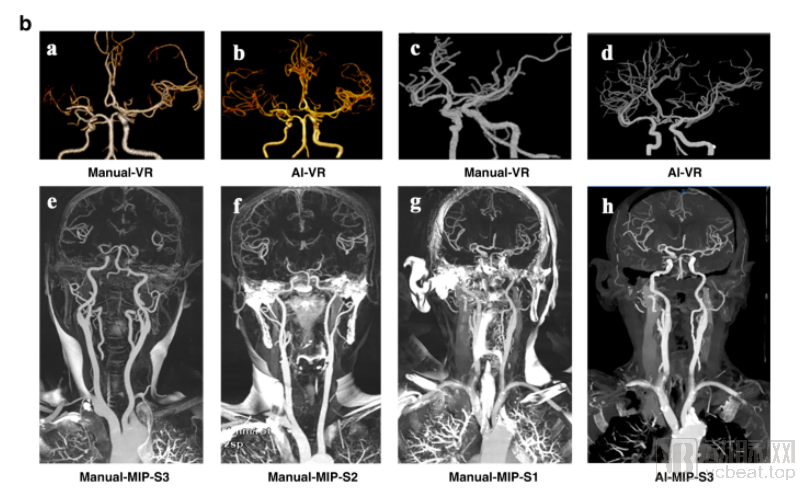

AI重建和手动重建图像质量的比较。第一行可见AI 重建图像血管管壁更加光滑,分支显示更远;第二行可见手动去骨受扫描的影响较大